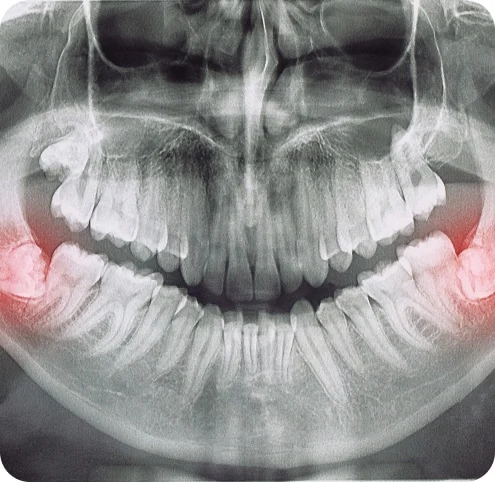

Insufficient space in the oral cavity for the complete eruption of third molars can lead to various complications. It is advisable to extract impacted wisdom teeth before their roots are fully formed, which can occur as early as 12 or 13 years old for some individuals, while others may experience this later in their early twenties. The likelihood of encountering problems tends to rise after the age of 30. Failing to remove your wisdom teeth can result in a range of potential issues.

Pericoronitis, a localized gum infection, is the most common clinical issue observed. Insufficient space for complete tooth eruption can lead to irritation and infection of the gum tissue surrounding the wisdom tooth. This, in turn, causes recurring pain, swelling, and difficulties with chewing and swallowing.

Non-communicable illnesses can also occur due to an impacted wisdom tooth. Cysts, which are fluid-filled sacs within the jaw bone, can develop and gradually expand, causing damage to nearby jaw bone and sometimes teeth. Treating these cysts can be challenging if wisdom teeth are not extracted during adolescence. While uncommon, tumors can be linked to the delayed removal of wisdom teeth.

The presence of impacted wisdom teeth can potentially lead to the overcrowding of your teeth, particularly the lower front teeth. This occurrence is frequently observed after a patient has undergone orthodontic treatment. Several factors can cause teeth to become crowded after braces or during early adulthood, with retained impacted wisdom teeth being one of them. The primary reason for their removal, unless there is an ongoing issue, is to safeguard your teeth, gums, and jaw bone from long-term damage.

Insufficient space for cleaning around the wisdom tooth may lead to negative consequences for the adjacent tooth, specifically the second molar. These consequences can include gum disease, bone loss around the tooth, and/or decay.